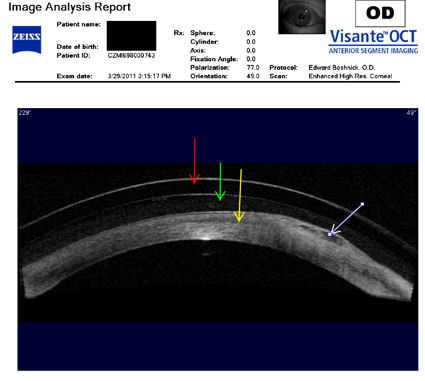

На изображении ниже представлен поперечный снимок глаза с буллезной кератопатией после операции LASIK. Пациент носит склеральную контактную линзу. Буллезная кератопатия - это состояние, при котором роговица становится постоянно опухшей вследствие повреждения самого внутреннего слоя роговицы, эндотелия. Эндотелий действует как насос, удаляя жидкость из роговицы для поддержания ее прозрачности.

Красная стрелка указывает на хрусталик склеры. Зеленая стрелка указывает на пространство между хрусталиком и роговицей, заполненное физиологическим раствором или слезами. Желтая стрелка указывает на роговицу. Крайняя правая стрелка указывает на область буллезной кератопатии.